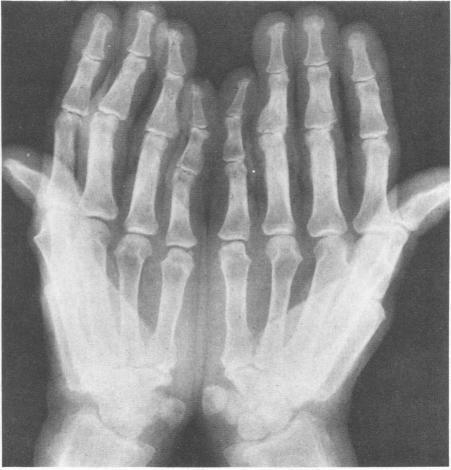

Herbert D A, Fessel W J

West J Med. 1981 Apr;134(4):354-7.